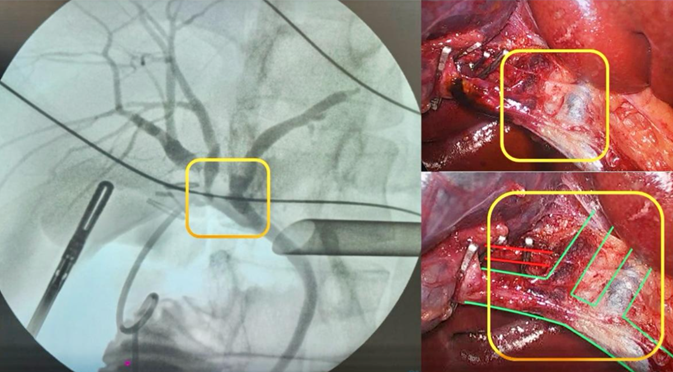

Fig.1 Colangiografía y visión quirúrgica de la laparoscopia esquematizada

Paciente masculino de 38 años sometido a colecistectomía laparoscópica programada por litiasis vesicular. Durante el acto quirúrgico se identificó una variante anatómica biliar infrecuente, consistente en el drenaje aberrante de un conducto hepático anterior directamente al conducto cístico, confirmada mediante colangiografía transcística. Las variantes del drenaje biliar derecho representan cerca del 20 % de las anomalías anatómicas, mientras que los conductos aberrantes constituyen aproximadamente el 2 % de las malformaciones biliares congénitas, con relevancia quirúrgica por el riesgo de lesión iatrogénica. 1 El caso destaca la importancia del conocimiento anatómico y del uso sistemático de la colangiografía intraoperatoria para una cirugía segura. Si bien clasificaciones como la de Blumgart resultan útiles para la identificación de variaciones biliares, esta anomalía no se ajusta a ninguna de sus categorías descritas. 2